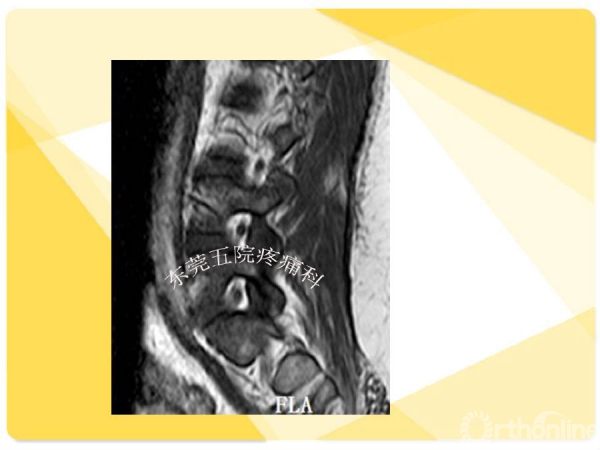

如何在椎间孔镜术前有效预防并发症的发生?如果不幸发生了该如何快速准确地处理?广东省东莞市第五人民医院疼痛科康健主任医师为大家分享了他的经验——